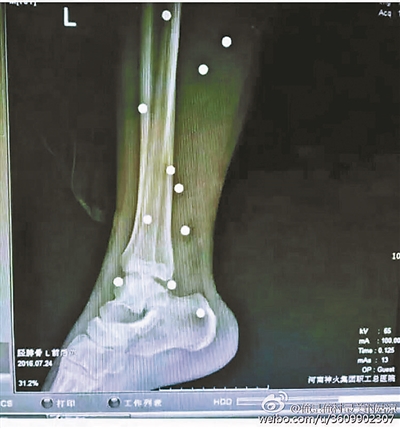

傷者體內取出的鋼珠

爆炸導致鋼珠遍布傷者身體各處

黃明的伯伯對北青報記者表示,由于黃明直接踩到了爆炸物,所以傷情最為嚴重,“他的腿被炸斷,身體內被炸進了40多顆鋼珠。手術后已經從體內取出29顆鋼珠,還有十多顆鋼珠沒有取出來?!备鶕S明的入院記錄,他全身有多處爆炸傷,且全身多處異物存留。

爆炸發生時,陳浩的位置與黃明靠得很近,因此也受傷較重。他告訴北青報記者,經過10多個小時的手術后,醫生從他身體里取出了12顆鋼珠。目前,他和黃明兩人經過手術后,已從重癥監護室轉至普通病房。其余三人中,陳剛的臀部受傷,當天晚上在醫院清理完傷口后便回了家,而同行的兩名女生身上有一些擦傷。